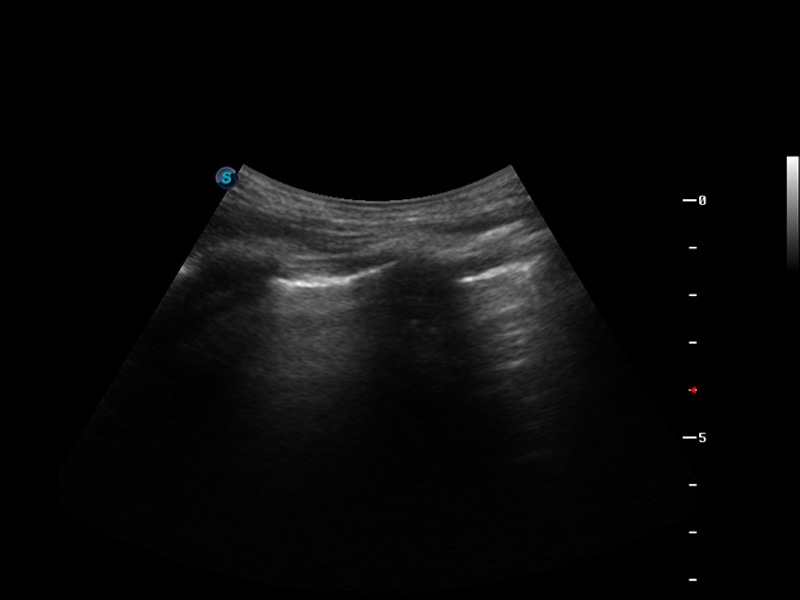

脉冲反相谐波成像